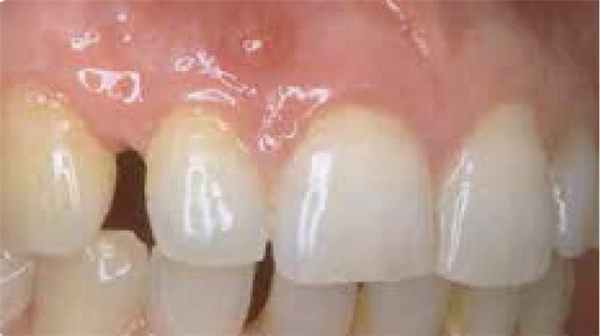

Симптомы и признаки гингивита

Простой гингивит сначала вызывает углубление борозды между зубом и десной, за которым следует образование полосы красной воспаленной десны вдоль одного или нескольких зубов, с отеком межзубных сосочков и легко индуцируемым кровотечением. Боль, как правило, отсутствует. Воспаление может разрешиться, оставаться поверхностным в течение многих лет, а в некоторых случаях прогрессировать до пародонтоза.

Гингивит

Обратимое воспаление десен, вызванное бактериями зубного налета. 2

Характеристики:

- Изменение цвета десны(или слизистой оболочки)

- Отек десневого края и сглаживание десневых сосочков

- Кровоточивость во время осмотра с использованием пародонтального зонда или во время чистки зубов

- Глубина прохождения зонда в десневую бороздку не более 3 мм

- Степень прилегания десны к зубам без изменений

Гингивит – воспаление десен

Это относительно легкая форма заболевания десен, от которой страдает большинство населения. Гингивит поражает только слизистые оболочки, розовые десневые ткани, окружающие челюстную кость, не затрагивая кость и не нарушая целостность механизма зубодесневого прикрепления. Гингивит может быть локальным или распространенным.

Симптомы болезни: покраснение, припухлость, кровоточивость десен во время механического воздействия и чистки зубов. Иногда о гингивите свидетельствуют глубокие зубодесневые карманы, но без потери кости (ложный карман). В подавляющем большинстве случаев гингивит не сопровождается болезненными ощущениями, и поэтому люди, как правило, не подозревают о существовании у них этого заболевания.